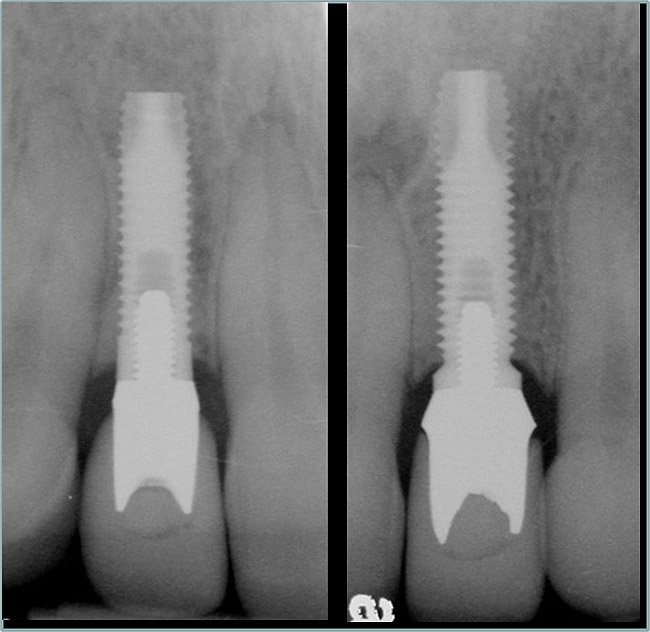

Figure 3  Periapical radiograph of implants in the Nos. 8 and 9 sites 3 years after placement. A bony peak was still present between the implants due to successful guided bone regeneration and favorable fixture spacing.

Figure 3

Figure 10   Periapical radiograph at the time of provisionalization. Note the wide peak of bone between implants Nos. 8 and 9.

Figure 10